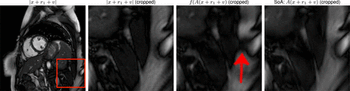

Side-by-side images show lung ultrasound pinpoints same findings as low-dose chest CT.